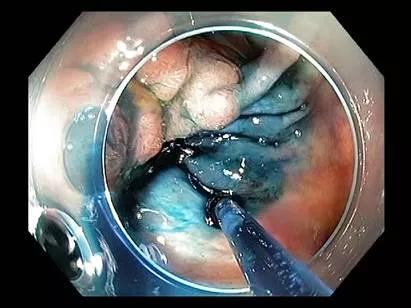

Endoscopic submucosal dissection (ESD) is an advanced endoscopy technique increasingly being used to remove large as well as complex lesions from the colon and rectum (as well as uses in the upper GI system).

ESD in the colon is different than in the upper GI system. The colonic wall is very thin, so performing these procedures in the stomach where it’s a thick lining is much safer than in the lower colonic area. This is why there was a lack of progress or experience gained by endoscopists in the colon area because of fear of perforation and complications. But as colorectal surgeons, we’re very familiar with the anatomy in that area and are in the unique position to be able to fix something immediately, if it were to occur. If intraluminal endoscopic techniques fail, combined endoscopic-laparoscopic surgery (CELS) using laparoscopic assisted polyp removal can be achieved before oncologic colorectal resections are needed (as shown in the images).